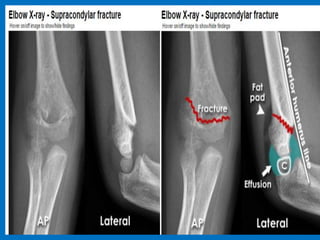

Typical supracondylar fracture. Fracture

is obvious on both the anteroposterior

(A) and lateral (B) views. Lateral view

demonstrates an abnormal relation of

the capitellum to the anterior humeral

line, which passes along the anterior

margin of the capitellum. Compare

these images with the lateral view of

the contralateral elbow (C), which

shows the anterior humeral line

passing normally through the middle

third of the capitellum.

Typical supracondylar fracture. Anteroposterior (A) and lateral (B) views.

Note the abnormal relation of anterior humeral line on the lateral view.

The radiocapitellar line does not pass through the capitulum.

In this case the ulna is also dislocated from the trochlea.